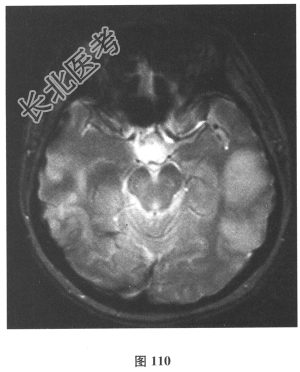

脑脊液检查:常规、生化均正常,CSF-病毒TORCH(-),抗Hu、Yo、Ri均阴性,OB、MBP正常。血清抗Hu、Yo、Ri均阴性。颅脑MRI显示左颞枕、右顶枕多发长T₁、长T₂信号,Flair高信号,病变累及皮质及皮质下白质,病灶无强化,见图108~图114。)根据颅脑MRI,需要鉴别的疾病应是